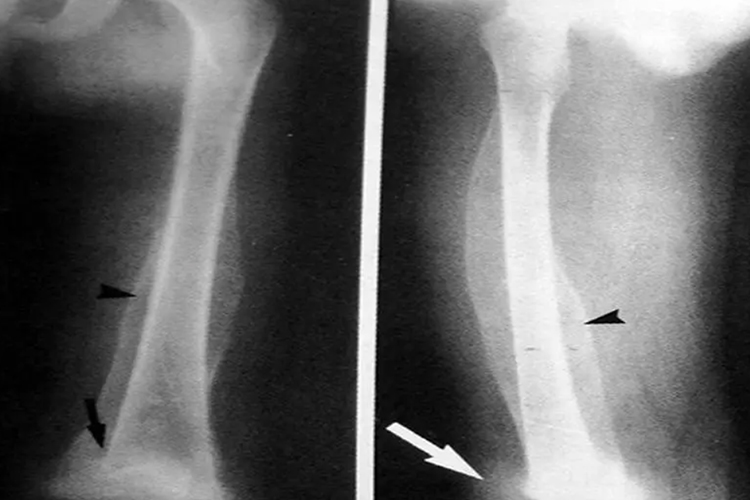

骨骼改变:小儿可有骨膜下出血,轻微活动引起剧烈疼痛,晚期长骨发育障碍,肋骨与肋软骨交界处有隆起,隆起之内侧有一凹陷。还可出现下肢假性瘫痪、髋关节外展膝关节半屈,呈蛙样姿势。X线检查可见长骨骺端出现白色骺线,骺线之下出现全宽度的黑色缝或倾角的黑色点。